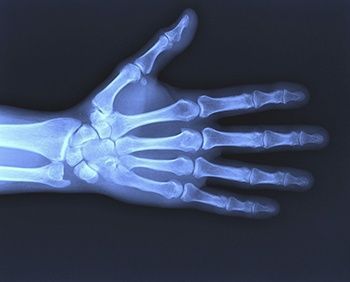

Рентген кисти

Кисть руки является дистальной частью верхней конечности, которая имеет сложное анатомическое строение. Рентген кисти представляет собой диагностическую методику, которая позволяет провести исследование её костных структур и суставов, оценить их состояние и выявить имеющиеся патологии и изменения, которые они вызвали. Своевременно проведённая диагностика позволяет исключить целый ряд серьёзных осложнений, ограничивающих подвижность кисти. Это актуально для любого пациента, поскольку руки и пальцы являются важнейшим инструментом человеческого тела, позволяющим выполнять большое количество задач.

Рентгенологическое исследование кисти руки позволяет получить данные о воспалительных процессах лимфоузлов, патологических процессах мышечных тканей и сухожилий. Благодаря ему хорошо просматривается вся структура кистей, их отделы, костные ткани, суставы, связки, а также любые их повреждения, начиная с трещин и заканчивая переломами.